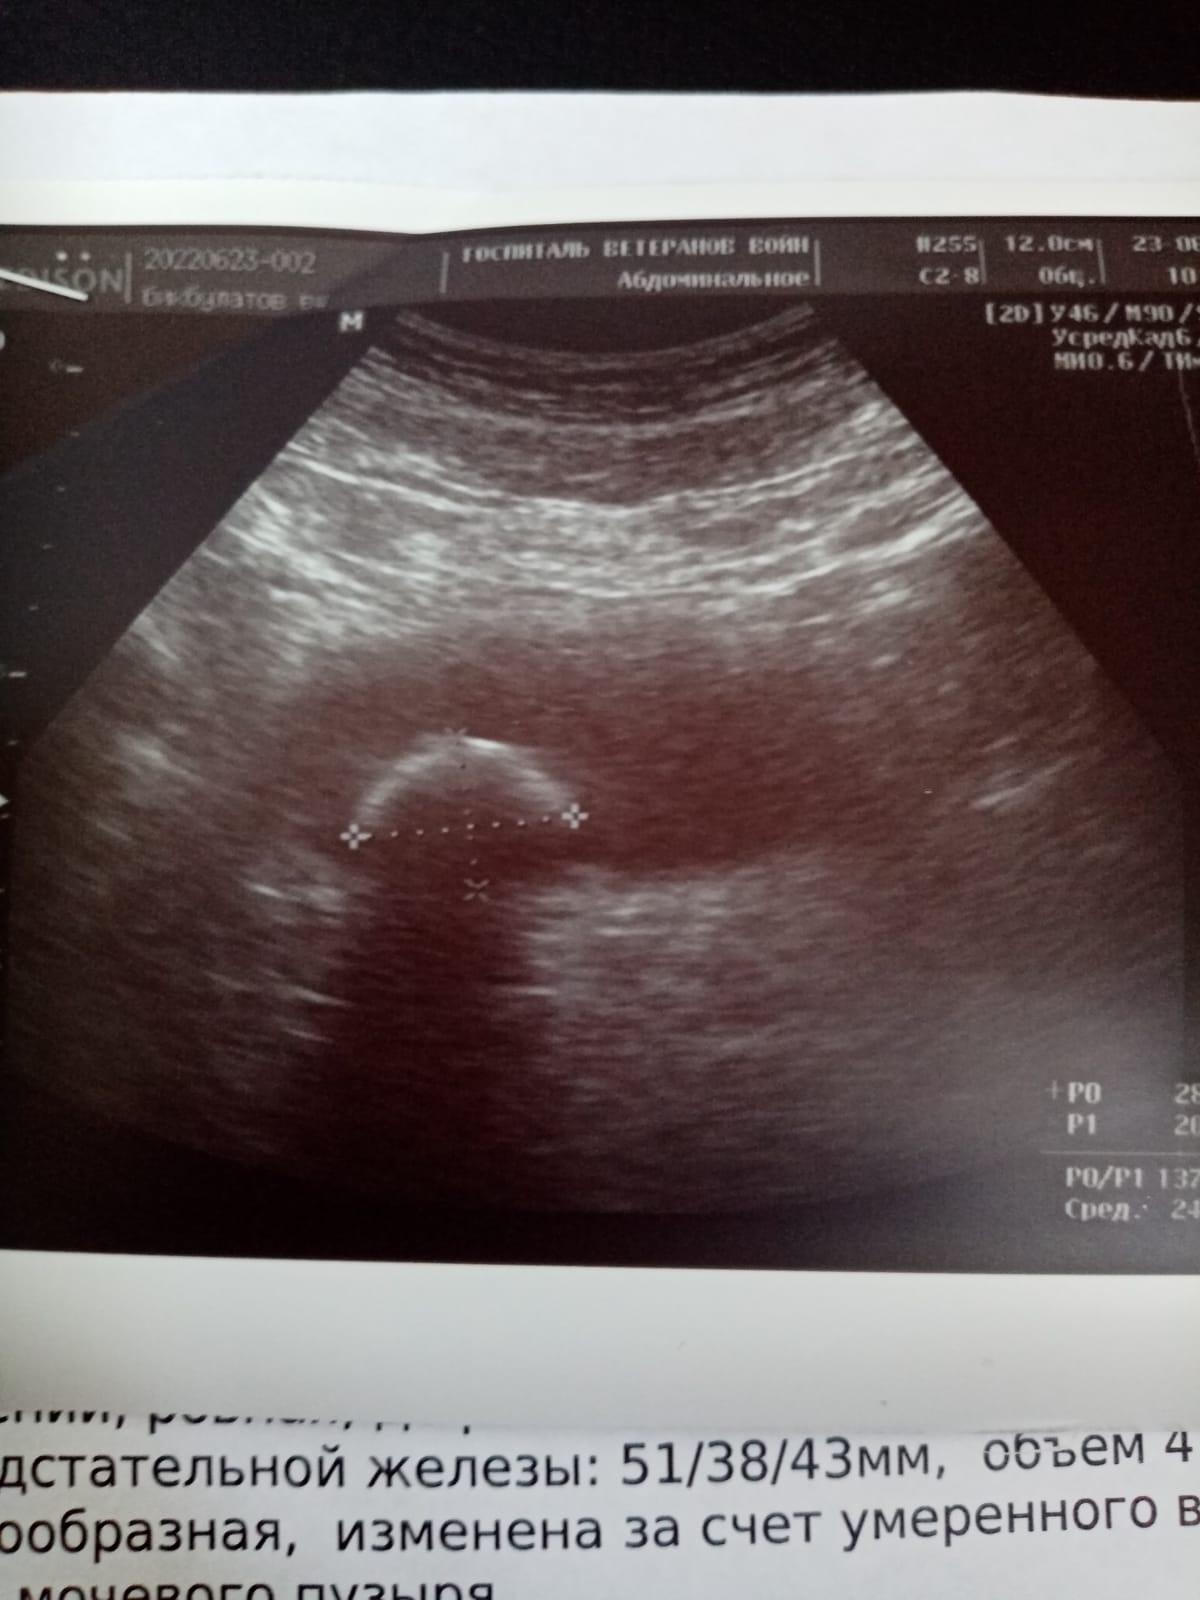

Добрый день! В Вашей ситуации, вероятнее всего, действительно придется оперироваться. Увеличение предстательной железы - аденома простаты/доброкачественная гиперплазия простаты - привела к нарушению оттока мочи и формированию в нем камня. Если не выполнить оперативное лечение (эндоскопическим путем можно удалить аденому и раздробить камень), то камень будет увеличиться, активизируется инфекция мочевых путей, будут страдать почки вплоть до развития хронической почечной недостаточности с самым неблагоприятным исходом. Поэтому не сомневайтесь и оперируйтесь. Главное - чтобы это делал опытный специалист. Удачи!